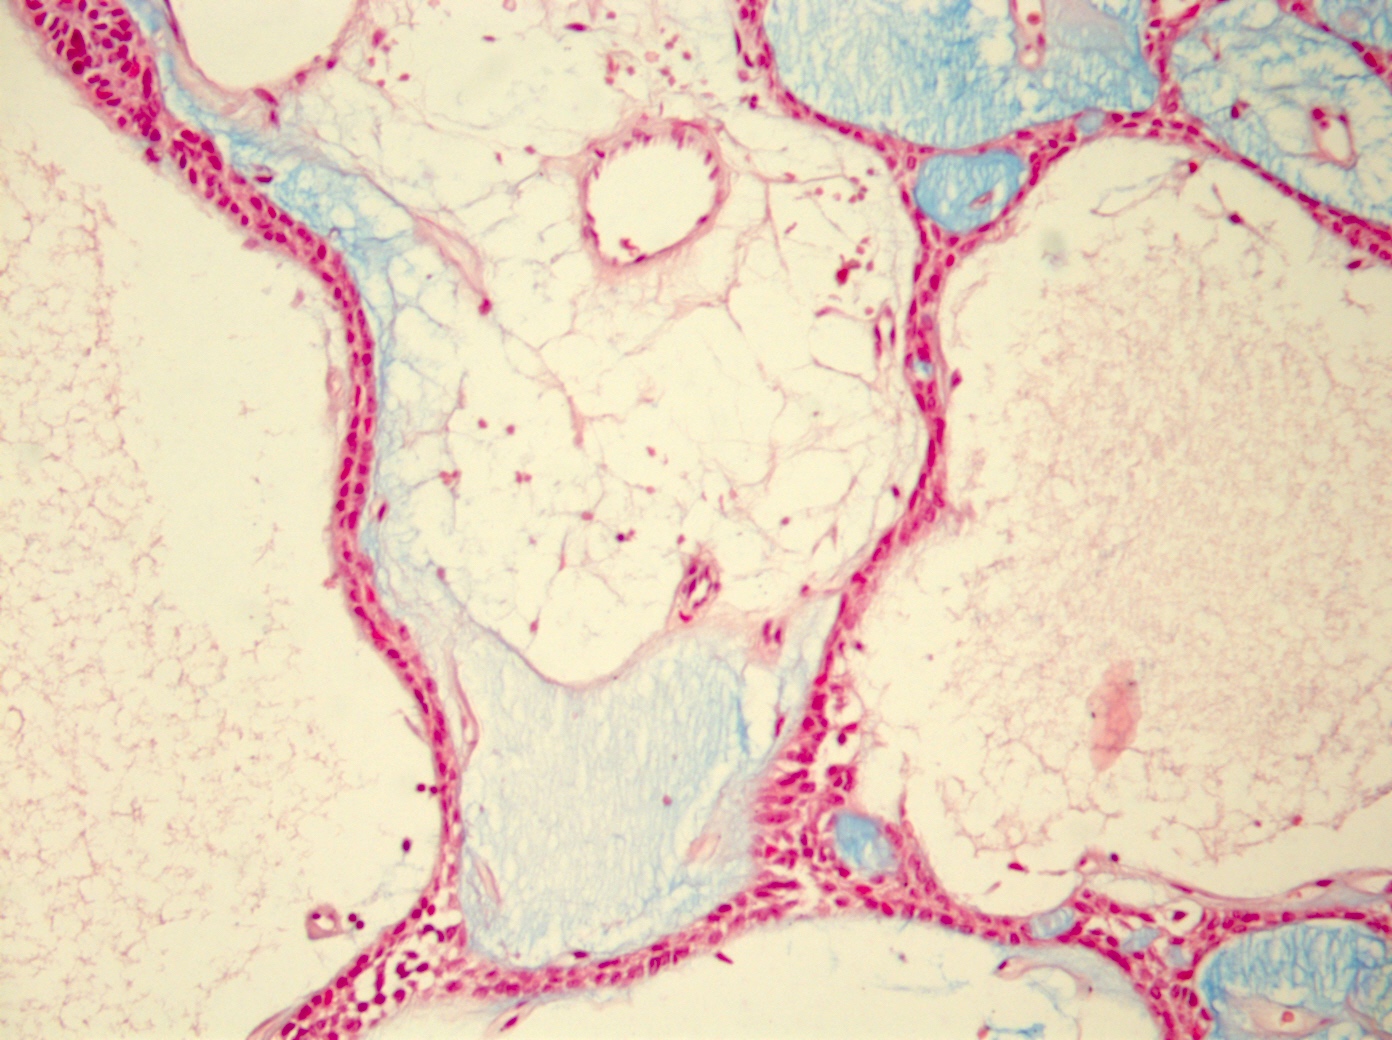

- Well vascularized, loose stroma; possibly sclerotic; perivascular eosinophil cuffs

- Luminal or stromal histiocytes (foamy, lipofuscin, hemosiderin), luminal hemorrhage, degenerated / infarcted stroma (Head Neck Pathol 2015;9:181)

Microscopic (histologic) images

- Stroma: blue on Alcian blue / PAS stain and CD15+ (Adv Ther 2019;36:1950)